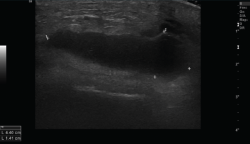

Ecografía

El ultrasonido se puede usar en el diagnóstico de numerosas patologías y puede guiar en procedimientos diagnósticos y terapéuticos(5).

Su indicación fundamental es en el diagnóstico de las lesiones de partes blandas superficiales.

Las estructuras específicas más adecuadas para este estudio incluyen tendones, músculos y ligamentos, además de masas periarticulares de tejidos blandos. Es útil para el diagnóstico de derrame articular, engrosamiento sinovial, bursitis, cuerpos libres intraarticulares, gangliones, quistes, roturas ligamentosas y tendinosas, tendinitis y fracturas ocultas(6).

En el estudio musculoesquelético se utiliza una sonda lineal con alta frecuencia, de entre 9 y 13 mHz.

1. Ligamentos

Tanto el ligamento lateral interno (LLI) como el ligamento lateral externo (LLE) pueden ser valorados por ecografía (Figura 7).

Figura 7. Corte coronal de una ecografía de rodilla. A: engrosamiento del ligamento lateral externo en la inserción proximal por un esguince de grado I; B: engrosamiento del ligamento lateral interno.